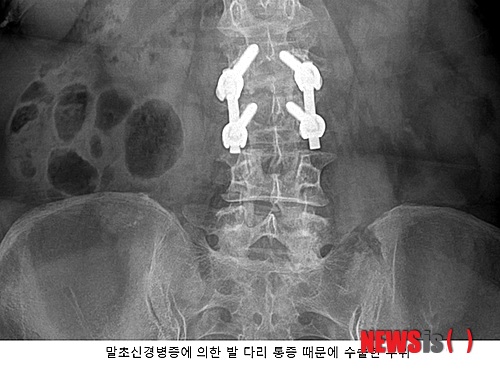

발·다리 저림 증상과 작열통증이 극심해졌고 결국 척추 디스크 수술을 받았다. 하지만 수술 후에도 발·다리 통증은 개선되지 않았다. 그러다 스템스 줄기세포 재생의학 클리닉에서 ‘말초신경병증’이라는 진단을 받고 신경강화주사 후 저림 증상과 작열통증이 호전되기에 이르렀다.